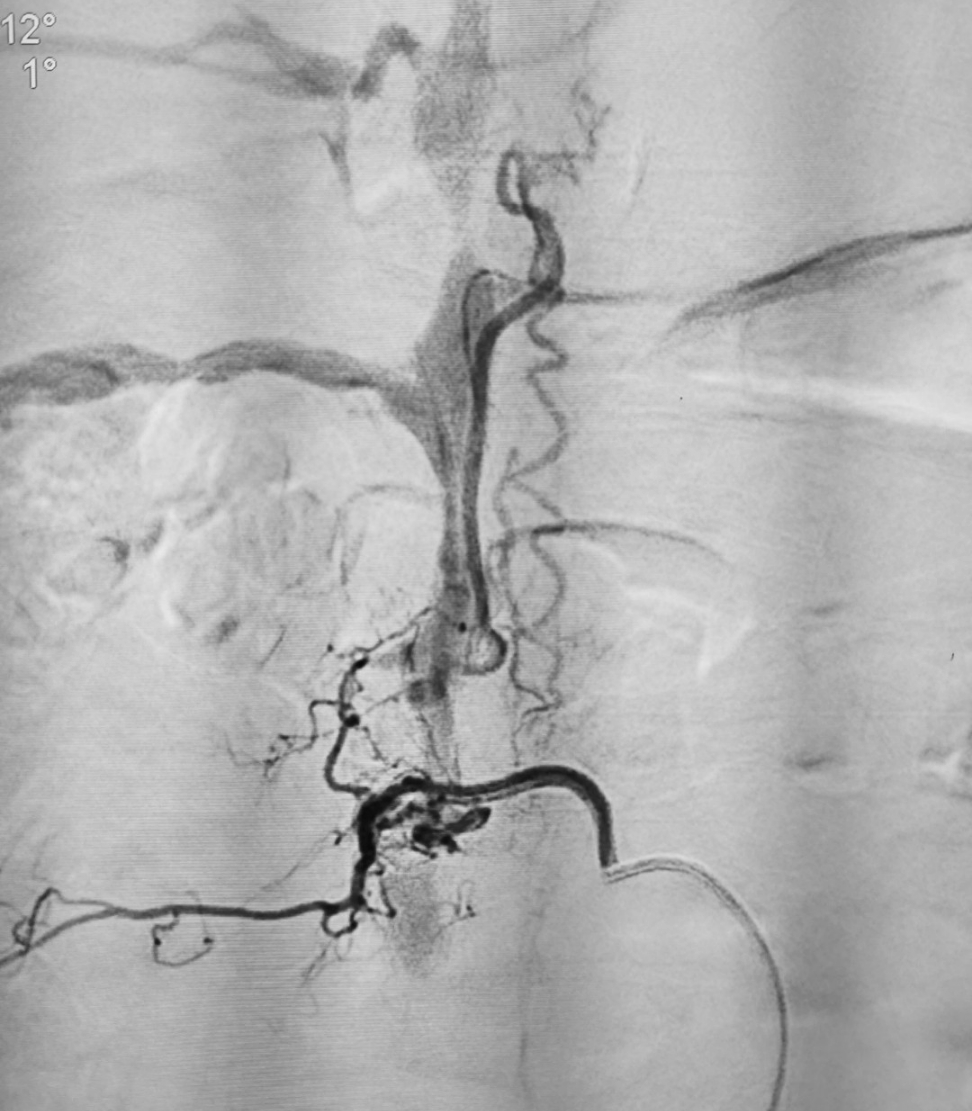

脊髓血管造影见肋颈干动脉供血的脊髓动静脉瘘